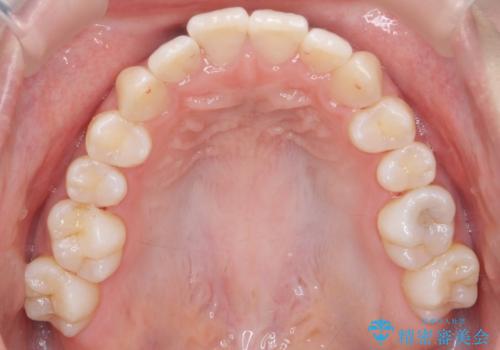

歯を抜かないで出っ歯を治したい

- 前歯が出ていることを主訴に来院。

歯を抜かずにマウスピース矯正をご希望でした。

歯と歯の間をわずかに削り、歯並びを少し横に拡大して並べました。

奥にすき間がなかったため後ろには下げていません。

沢山ひっこめるには4本抜歯でワイヤーの選択肢もありましたが、抜かないでできる範囲をご希望されました。

とがった形の歯列を整えるだけでもだいぶ印象は変わると思います。

今回歯列を広げた結果、上顎犬歯の歯肉は多少退縮しています。